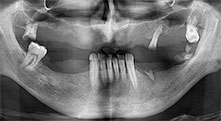

Professor Dr. Dr. Emanuel Bratu, maxillofacial surgeon, oral surgeon and prostheticist, is head of the implantology departments at two Romanian universities. He runs a renowned private hospital in Timisoara and is an internationally known researcher. In the interview Bratu explains why he considers that the W&H Piezomed piezosurgical device, and particularly two patented saws, have become essential for bone surgery.

Professor Bratu, what is your experience with the new B6/B7 saws for the W&H Piezomed?

Bratu: These saws feel completely different from previously available piezosurgical instruments. They are really astoundingly effective. We noticed immediately that the Piezomed B6/B7 work much faster than other saws. They are also easier to guide in bone, particularly in thick bone layers.

According to W&H this is due to the high power output of the surgical unit combined with the very fine teeth and the small diameter of the saw blades of only 0.25 mm.